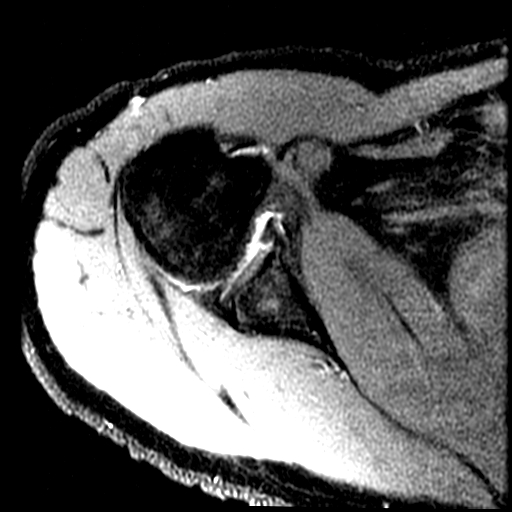

Figure 1 for case GLAD lesion

Figure 1

Partial tear of the anterior inferior labrum with a small peripheral defect of the adjacent glenoid articular cartilage. Anterior scapular periosteum remains intact. Reference article.

GLAD lesion